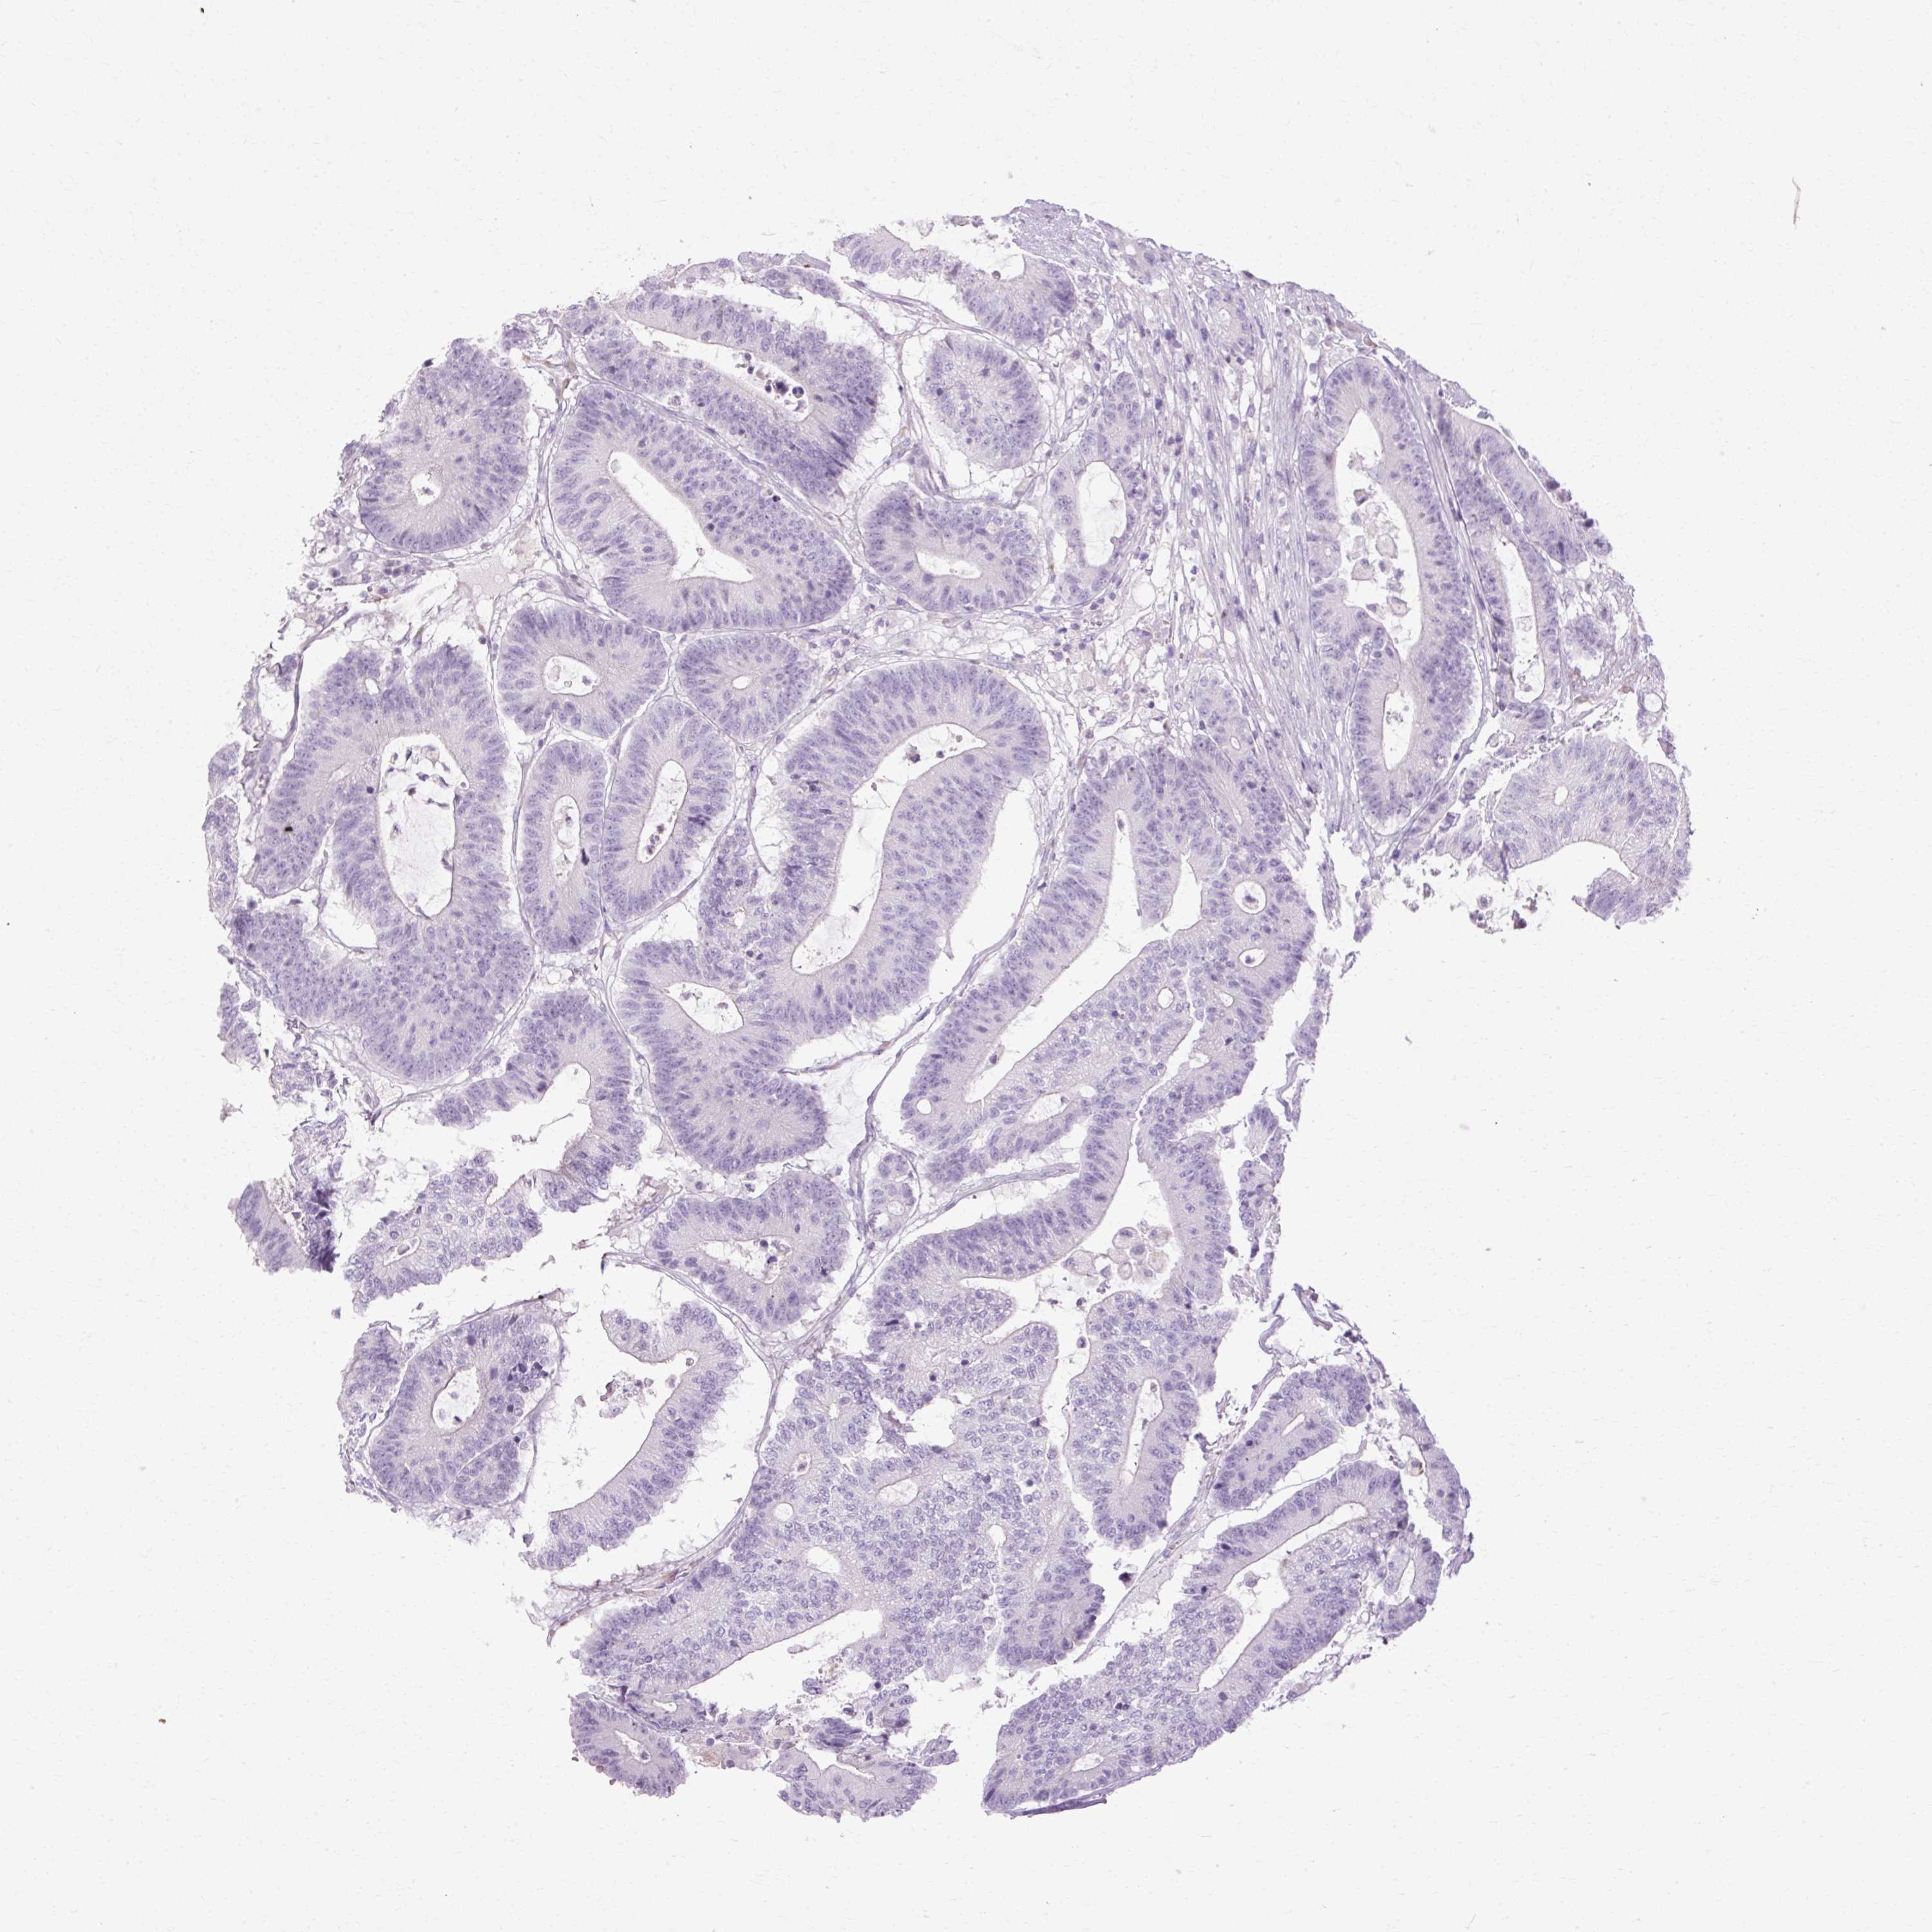

Colorectal cancer

Colon adenocarcinoma